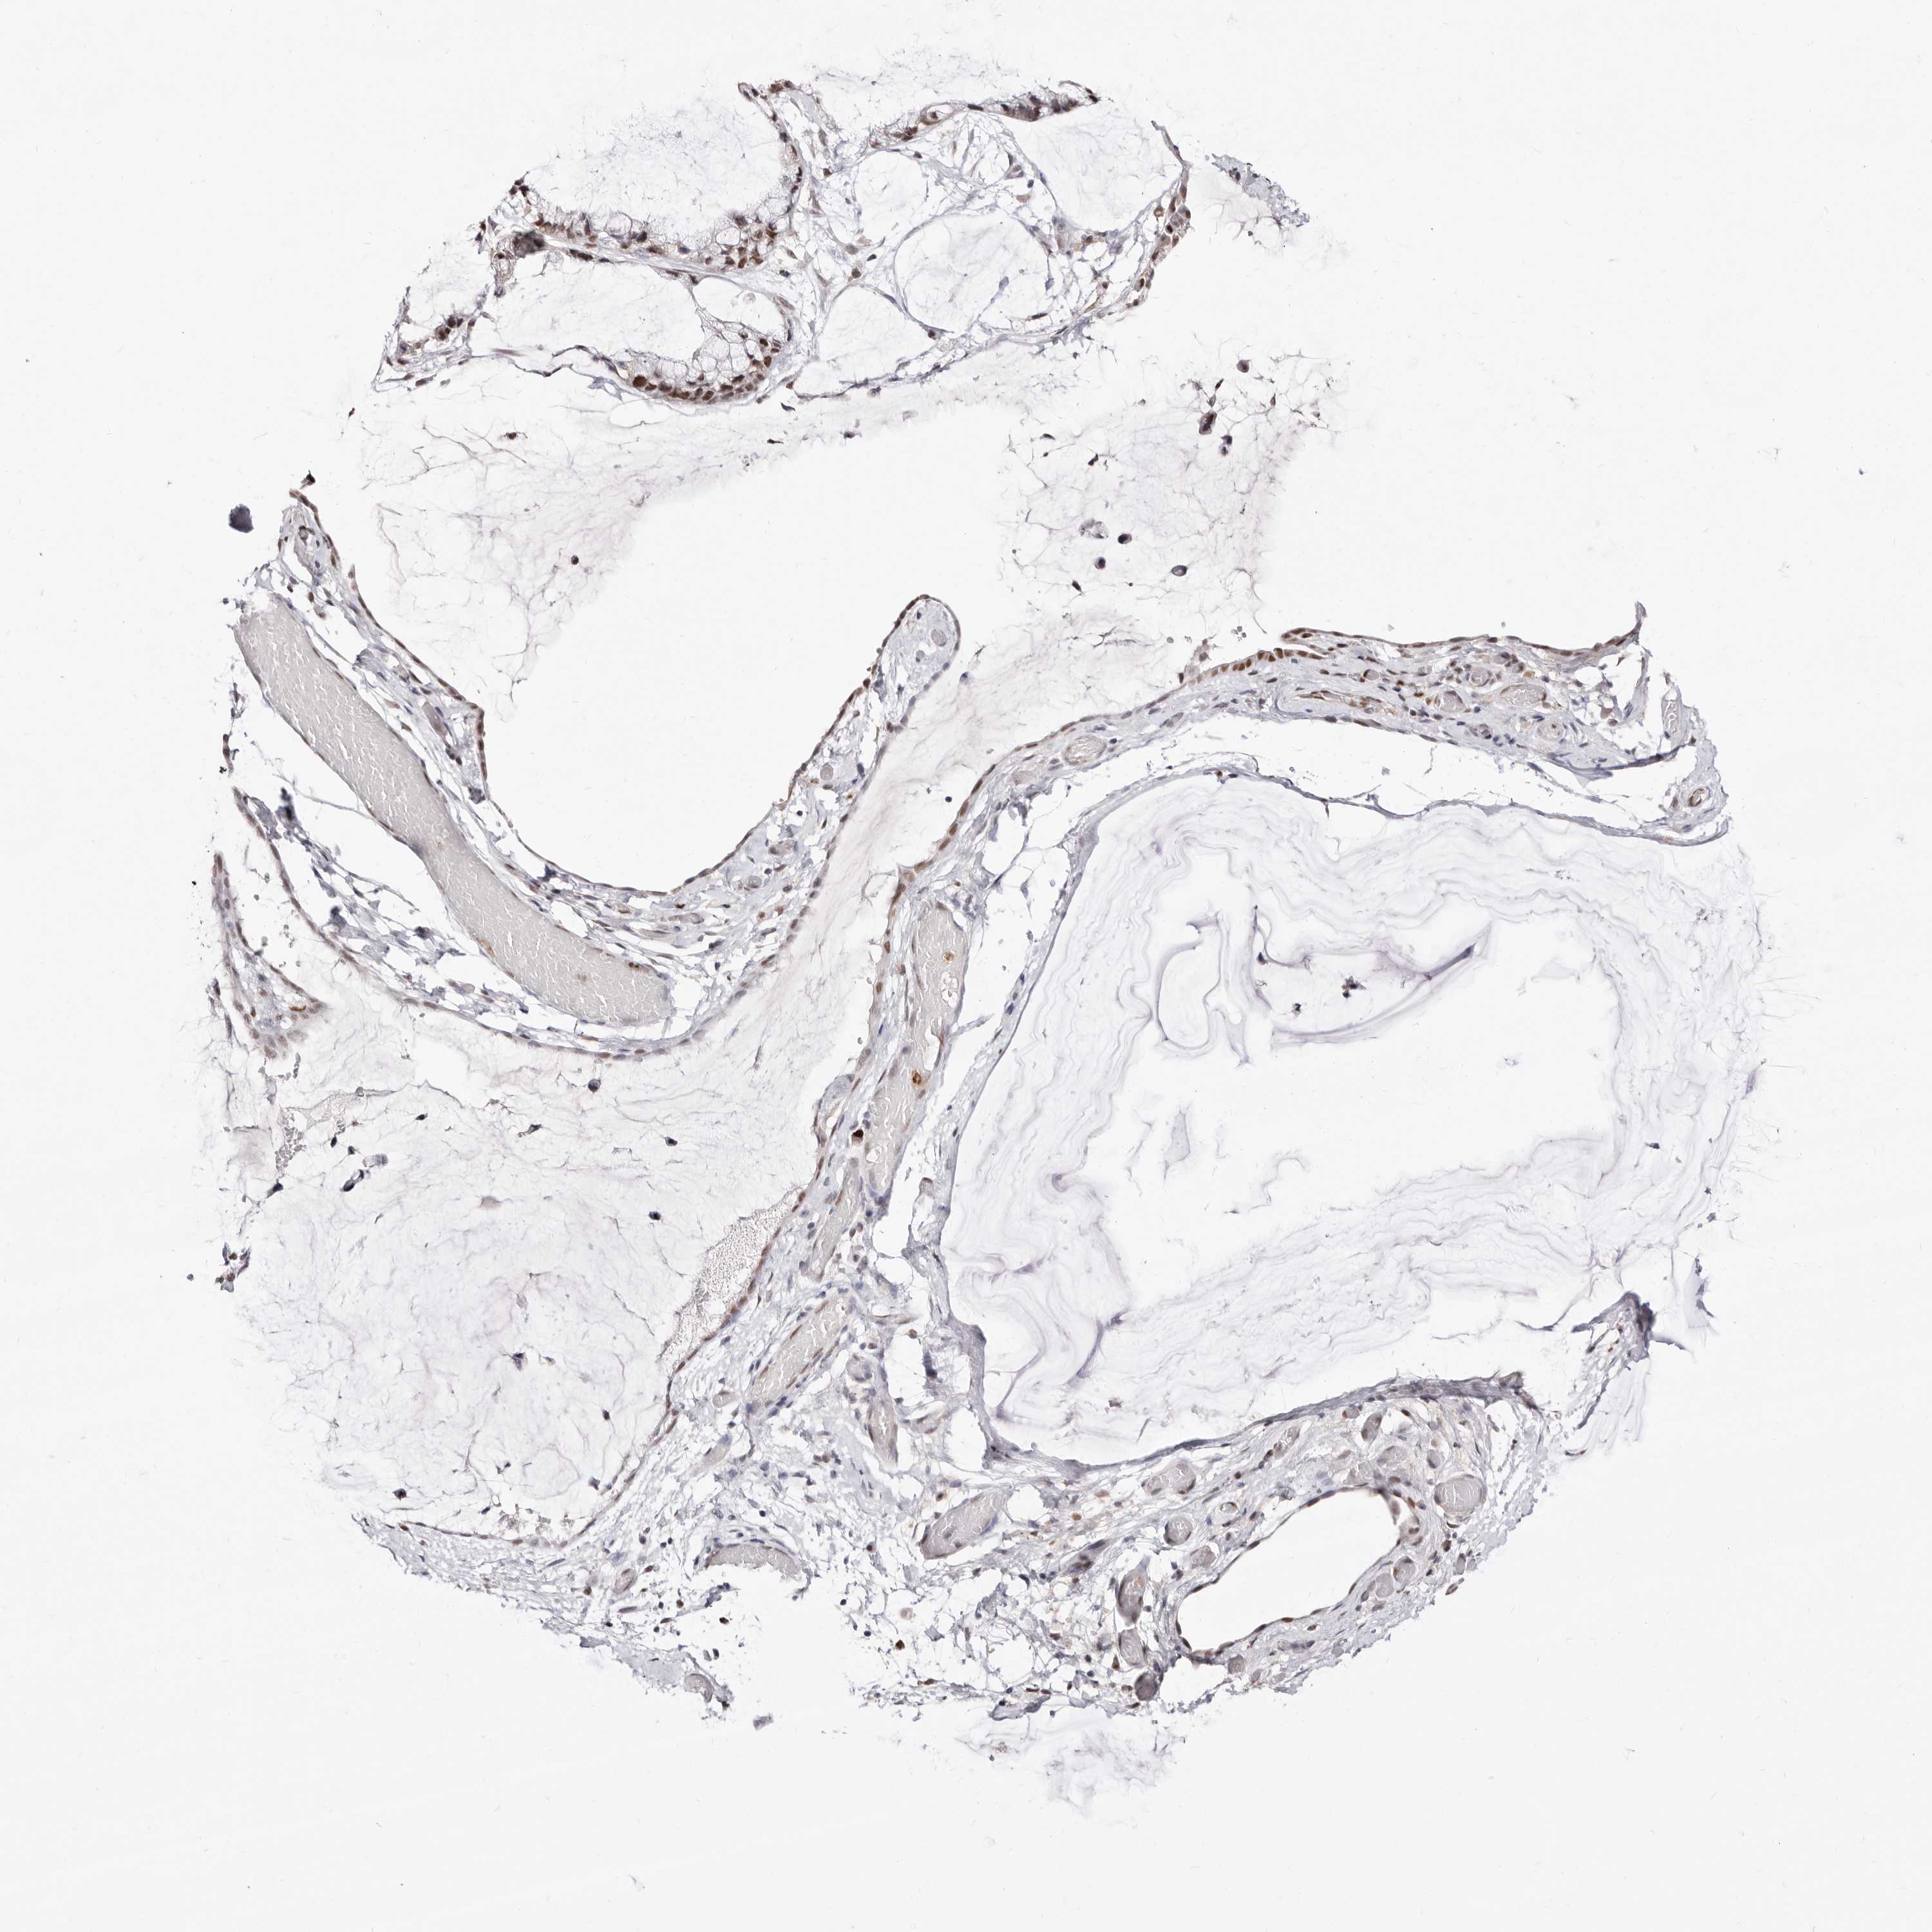

OVARIAN CANCER - Protein expressioni

A mouse-over function shows sample information and annotation data. Click on an image to view it in a full screen mode. Samples can be filtered based on level of antibody staining by selecting one or several of the following categories: high, medium, low and not detected. The assay and annotation is described here.

Note that samples used for immunohistochemistry by the Human Protein Atlas do not correspond to samples in the TCGA dataset.

Antibody stainingi

Antibody staining in the annotated cell types in the current human tissue is reported as not detected, low, medium, or high, based on conventional immunohistochemistry profiling in selected tissues. This score is based on the combination of the staining intensity and fraction of stained cells.

Each image is clickable and will lead to virtual microscopy that enables deeper exploration of all samples and also displays staining intensity scores, fraction scores and subcellular localization as well as patient and tissue information for each sample.

Antibody HPA029480

Antibody HPA029481

Cystadenocarcinoma, serous, NOS

Carcinoma, endometroid

Cystadenocarcinoma, mucinous, NOS

Carcinoma, NOS